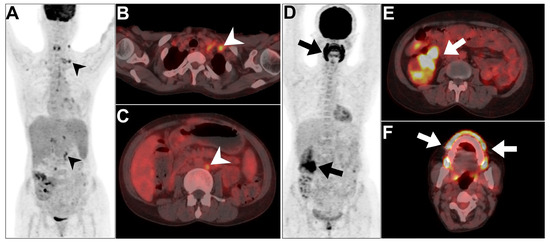

2.1.2. Infective Polycystic Kidney Disease

2.3.1. Chronic Pyelonephritis

2.3.2. Renal Abscess